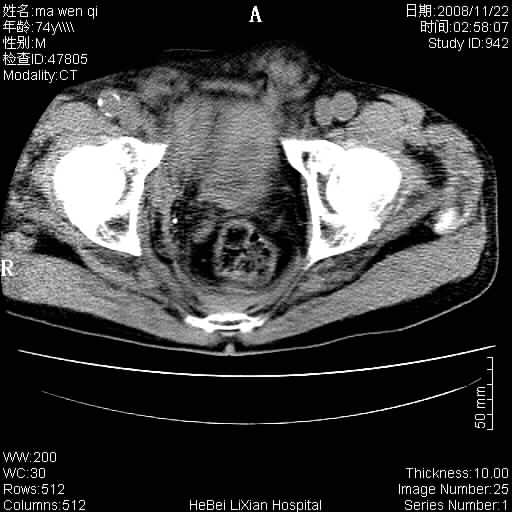

患者男 74岁.突然昏迷,休克6小时.血压70/30,头颅ct未见异常,既往体健.

补充病史,保留导尿10小时,尿袋内只有少许尿液,患者于住院后15小时后去世.

腹主动脉、双侧髂动脉夹层动脉瘤破裂出血进入腹腔。

考虑双侧髂a瘤,伴破裂出血

腹主动脉、双侧髂动脉夹层或动脉瘤破裂出血进入腹腔

1)考虑双侧髂动脉瘤并右侧动脉瘤破裂出血,右侧腹膜后及腹腔积血。2)双侧腹股沟疝。

支持(1)双侧髂动脉瘤并右侧动脉瘤破裂出血,右侧腹膜后及腹腔积血。(2)双侧腹股沟疝。

1)考虑,腹主动脉、双侧髂动脉夹层动脉瘤破裂伴右侧腹膜后及腹腔积血。2)双侧腹股沟疝。